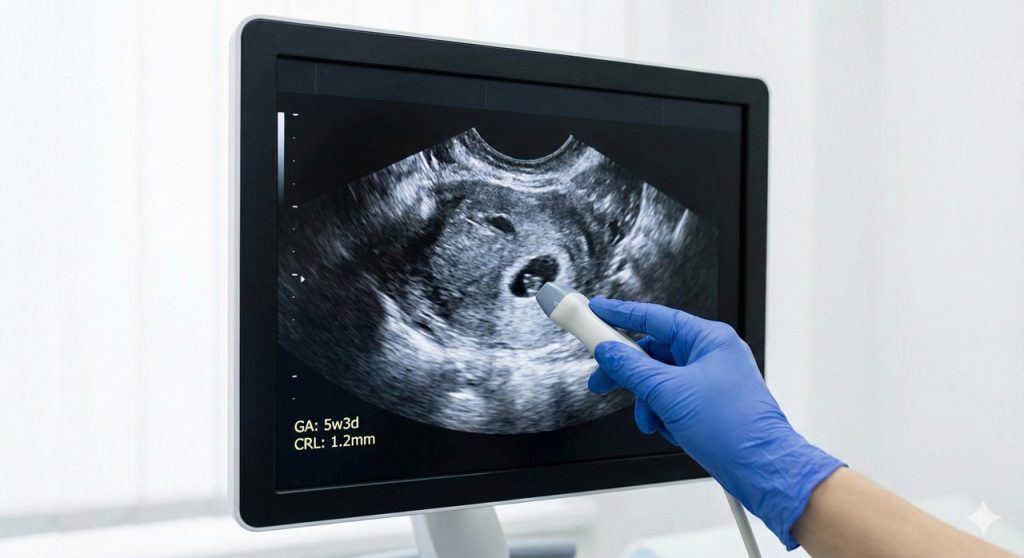

Ultrasounds can detect pregnancy as early as 4 weeks after your last menstrual period. However, the type of ultrasound makes a big difference. A transvaginal ultrasound can detect pregnancy slightly earlier than an abdominal ultrasound because the probe is placed closer to the uterus, providing clearer images.

At 4 weeks, a small gestational sac may be visible inside the uterus. By week 5, the yolk sac develops, and the embryo may start to appear. By week 6, you can often see the fetal heartbeat, which is one of the most reassuring signs of a viable pregnancy.

A transvaginal ultrasound involves inserting a small, wand-like probe into the vagina. This method provides high-resolution images of the uterus, making it the preferred choice for early detection. It can detect pregnancy as early as four weeks after your last menstrual period and gives a clearer view of early structures such as the gestational sac, yolk sac, and embryo.

- Week 4: Gestational sac may be visible with transvaginal ultrasound.

- Week 5: Yolk sac forms, embryo may start appearing; heartbeat may be detected in some cases.

- Week 6: Embryo is more clearly defined, and heartbeat detection becomes more consistent.